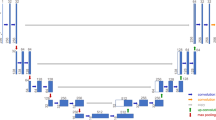

As shown in Fig. 2, the disease did not affect the anatomical features of the spinal canal or the SC. The spinal cord volume was similar in ALS patients and in control subjects, both in the cervical district (32.08 ± 7.12 mL vs. 31.36 ± 5.99 mL, respectively, p = 0.79) and in the dorsal district (65.60 ± 10.09 mL vs. 68.84 ± 12.61 mL, respectively, p = 0.10,; Fig. 2a–e).The extracted SC volume was also similar in patients and control subjects both in the cervical segment (13.99 ± 1.42 mL vs. 13.53 ± 1.60 mL, respectively, p = 0.47, ns) and in the dorsal segment (32.60 ± 3.22 mL vs. 32.81 ± 4.25 mL, respectively, p = 0.56; Fig. 2b). As for the spinal canal, ideal body weight was directly correlated with overall SC volume in control subjects, but the significance of this relationship was lower in ALS patients (Fig. 2f).

a Sagittal whole-body CT scan (left) and the corresponding image showing extraction of the cervical (red) and dorsal (green) spinal canal. b–d Volumes of the spinal canal (solid bars) and spinal cord (hatched bars) in the control subjects (CTR) and in the 30 ALS patients (ALS): b total volumes, c cervical region, d dorsal region. There are no differences between the control subjects and ALS patients. e, f Linear regression analysis of the relationship between spinal canal volume (e) and spinal cord volume (f) and ideal body weight